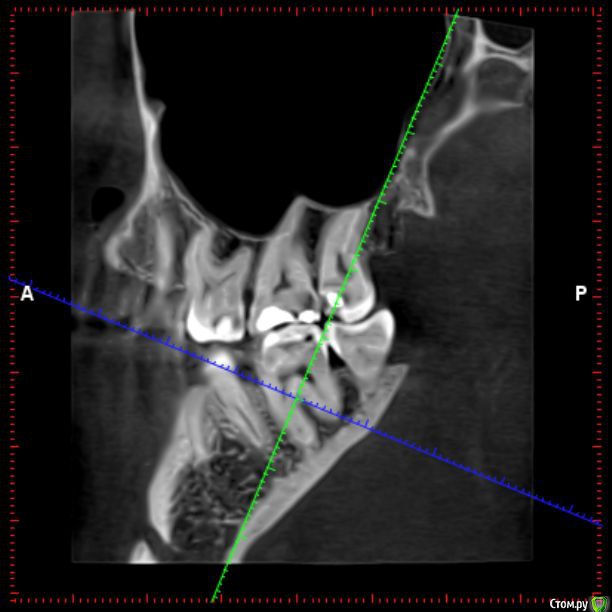

Здравствуйте! Откололся кусок зуба. 8 октября сделали КЛКТ (3Д снимок всех зубов). Вскрыли зуб, была проведена девитализация. Поставили диагноз: хронический фиброзный пульпит 37 зуба. 18 октября было проведено первичное лечение 3-х канального зуба эндомотором с использованием микроскопа и системы коффердам. Все каналы были запломбированы гуттаперчивыми штифтами на силлере методом латеральной конденсации Adseal, внутрь заложена ватка и поставлена временная пломба дентин-паста. 29 октября ортопед №1 посмотрел прицельный снимок (см. снимок зуба 2) и сам зуб, пломбу не снимал. Озвучил, что у меня низкая высота зуба, мне нужно установить культевую кобальт-хромовую вкладку и сверху покрыть металлокерамической коронкой зуб. Также сказал, что циркониевая вкладка мне не подходит из-за высоты. Однако, поскольку ортопед №1 уходил на обучение, мне было предложено обратиться в другую клинику к другому ортопеду. 1 ноября ортопед №2 посмотрев мой зуб без снимка заявил, что у меня сохранились три стенки у зуба и мне надо просто закрыть пломбой этой зуб. Поскольку ортопед №2 предложил диаметрально противоположное лечение зуба, то я решил обратиться в третью клинику. Ортопед №3 посмотрев снимок моего зуба, сам зуб, в том числе внутри (снял мою временную пломбу из дентина), заявил, что у меня низкая высота зуба и мне нельзя ставить культевую вкладку и коронку. И было предложено сделать вкладку из пресс керамики overlay. Также когда удалили временную пломбу у меня увидели кариес на этом зубе. В конце приема мне взамен снятой пломбы установили временную пломбу парасепт.

Спасибо за ответ. Перевернул снимок. Прицельного снимка до лечения не делали, только КЛКТ. Не знаю насколько подойдет снимок из КЛКТ, но прикрепил. Я правильно Вас понял, что мне пролечили плохо каналы под микроскопом, в частности дистальный канал, тк гуттаперча вышла за пределы корня? Мне нужно повторно перелечить этот канал под микроскопом?